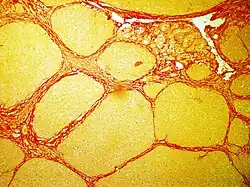

Sirius Red F 3B (Direct Red 80) is an azo dye primarily used in staining methods for collagen and amyloid.[1] It has the molecular formula C45H26N10Na6O21S6.

In histology, sirius red staining is used in various domains of diagnostic to observe fibrosis levels in a lot of cases of inflammation induced by cancer, vascular or metabolic pathologies.[2]

In bright field microscopy the following can be observed:

- The nuclei in yellow

- The cytoplasm in yellow

- Collagen fibers in red

- Muscular fibers in yellow

- Red blood cells in yellow